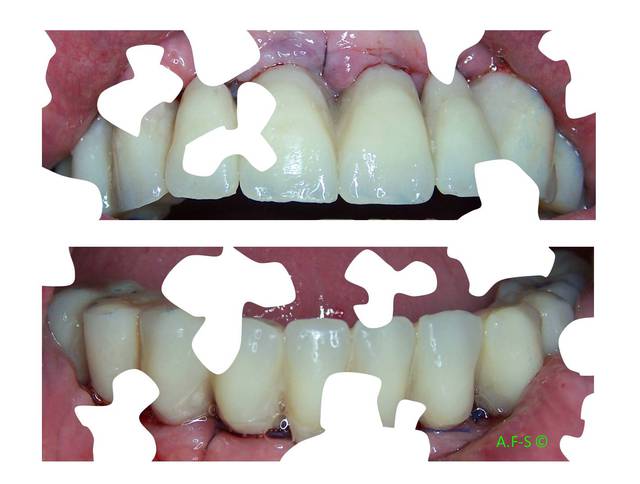

Extraction, pose d’implants Ankylos, pose des piliers Standard définitifs, mise en charge immédiate bi-maxillaire en une chirurgie.

Maxillaire supérieur – extraction 13, 26, 7 implants en MCI, 1 implant en MCR pose summeurs, densification par ostéotme, comblement osseux, bridge provisoire sans fausse gencive avec renfort métallique.

Maxillaire inferieur – extraction 35, 34, 44, 45, 6 implants MCI, comblement osseux, bridge provisoire sans fausse gencive avec renfort métallique.

Le patient présente une perte de DV importante qui doit être corrigé avec les bridges provisoires.

Esthétique

Préopératoire